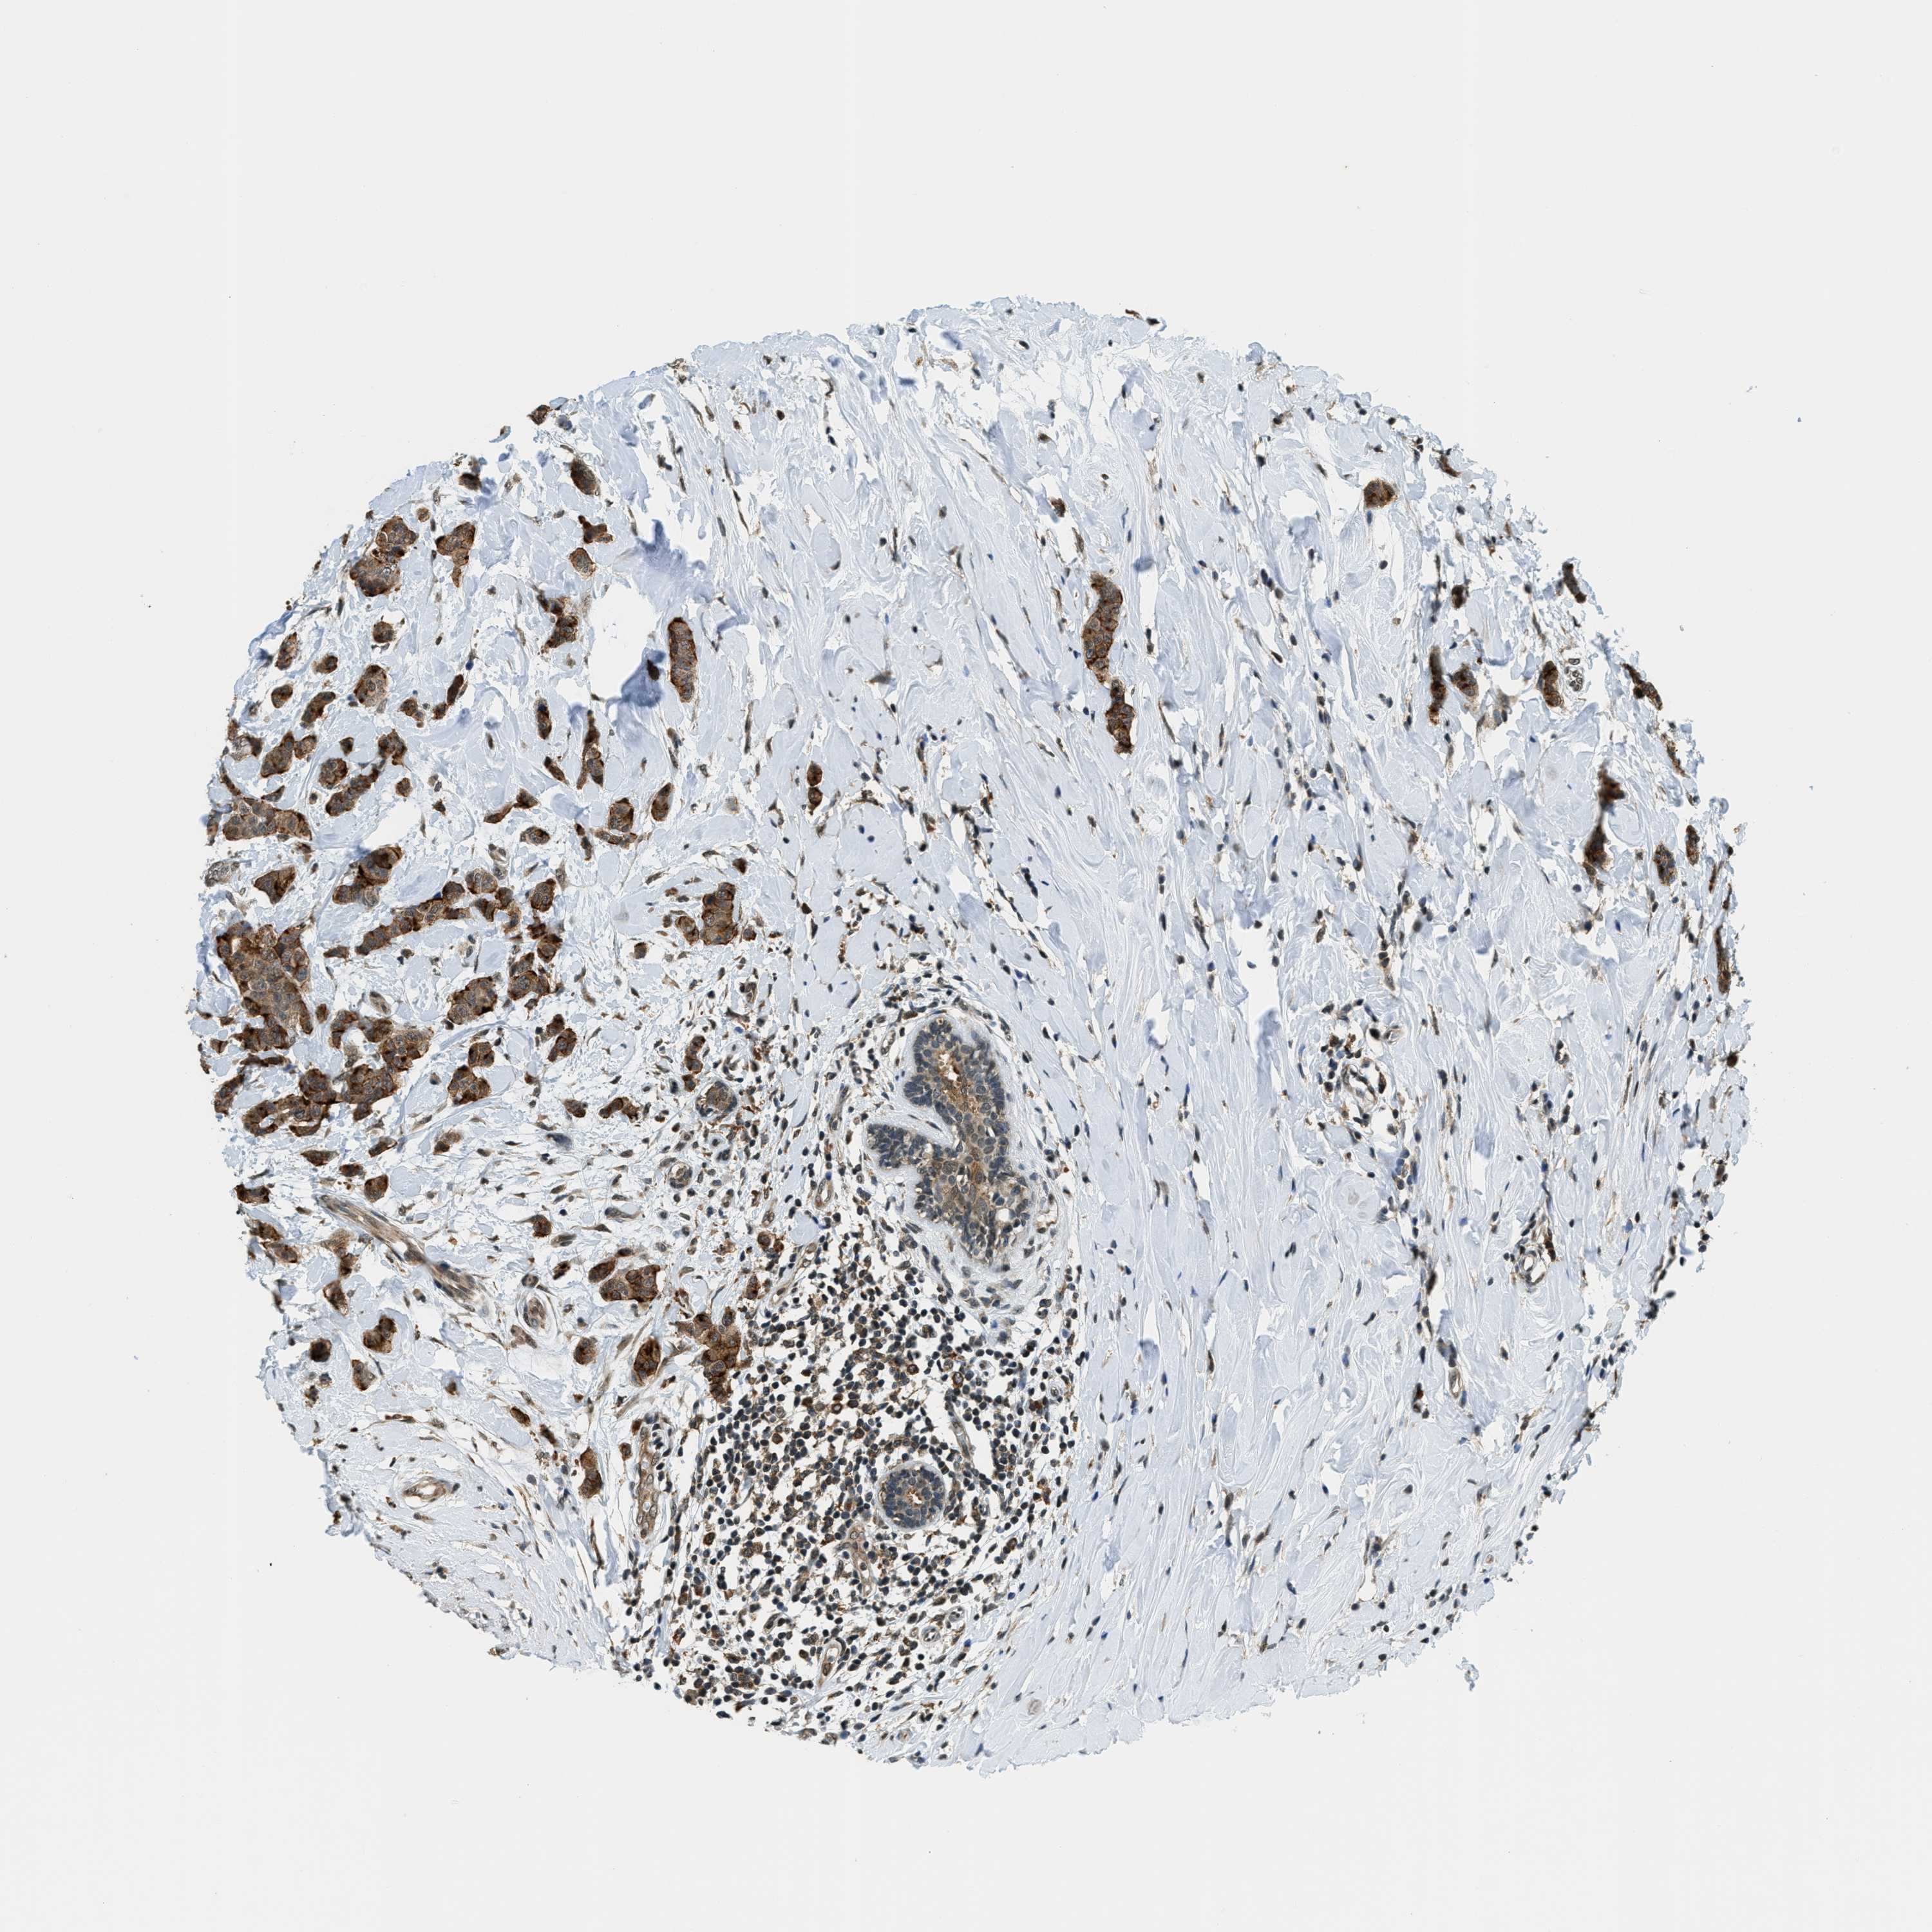

CANCER BREAST CANCER Show tissue menu

BRCA TCGA BRCA VALIDATION PROTEIN EXPRESSION